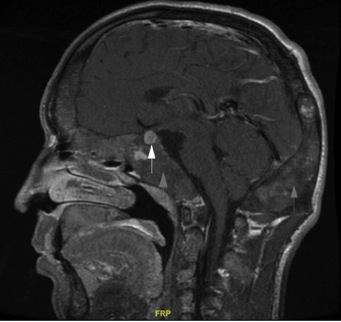

- На МРТ головного мозгавизуализирована микроаденома аденогипофиза размерами 7×6 мм (рис. 3) с инфраселлярным распространением, а также признаки диффузного утолщения левой верхнечелюстной и клиновидной пазух, клиновидной кости, латеральной стенки левой глазницы, базилярной части затылочной кости по типу фиброзной дисплазии (рис. 4).

Рис. 3. Пациентка М. МРТ головного мозга. Микроаденома гипофиза с пара-инфраселлярным распространением.

Описание. Турецкое седло деформировано, в правой части дно турецкого седла локально углублено. Структура аденогипофиза неоднородна за счет кистозно-солидного образования в его правой части, размерами 7×6 мм. Образование распространяется в пазуху основной кости.

Рис. 4. Пациентка М. МРТ. Фиброзная дисплазия клиновидной кости.

Описание. Субтотальная обтурация пазухи основой кости. В левой верхнечелюстной пазухе, преимущественно по передней стенке, в левой клиновидной пазухе и клиновидной кости (теле и левом крыле), в задних ячейках решетчатого лабиринта, базилярной части затылочной кости (больше слева), в латеральной стенке левой глазницы, в затылочной чешуе определяется диффузное утолщение костей по типу фиброзной дисплазии, с наличием в структуре кистозных включений.